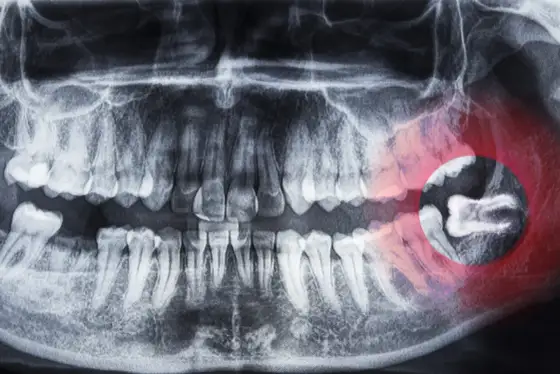

Dowiedz się, czym płukać jamę ustną po wyrwaniu ósemki, aby uniknąć bólu i przyspieszyć gojenie. Sprawdź bezpieczne metody płukania, domowe sposoby i porady pielęgnacyjne.